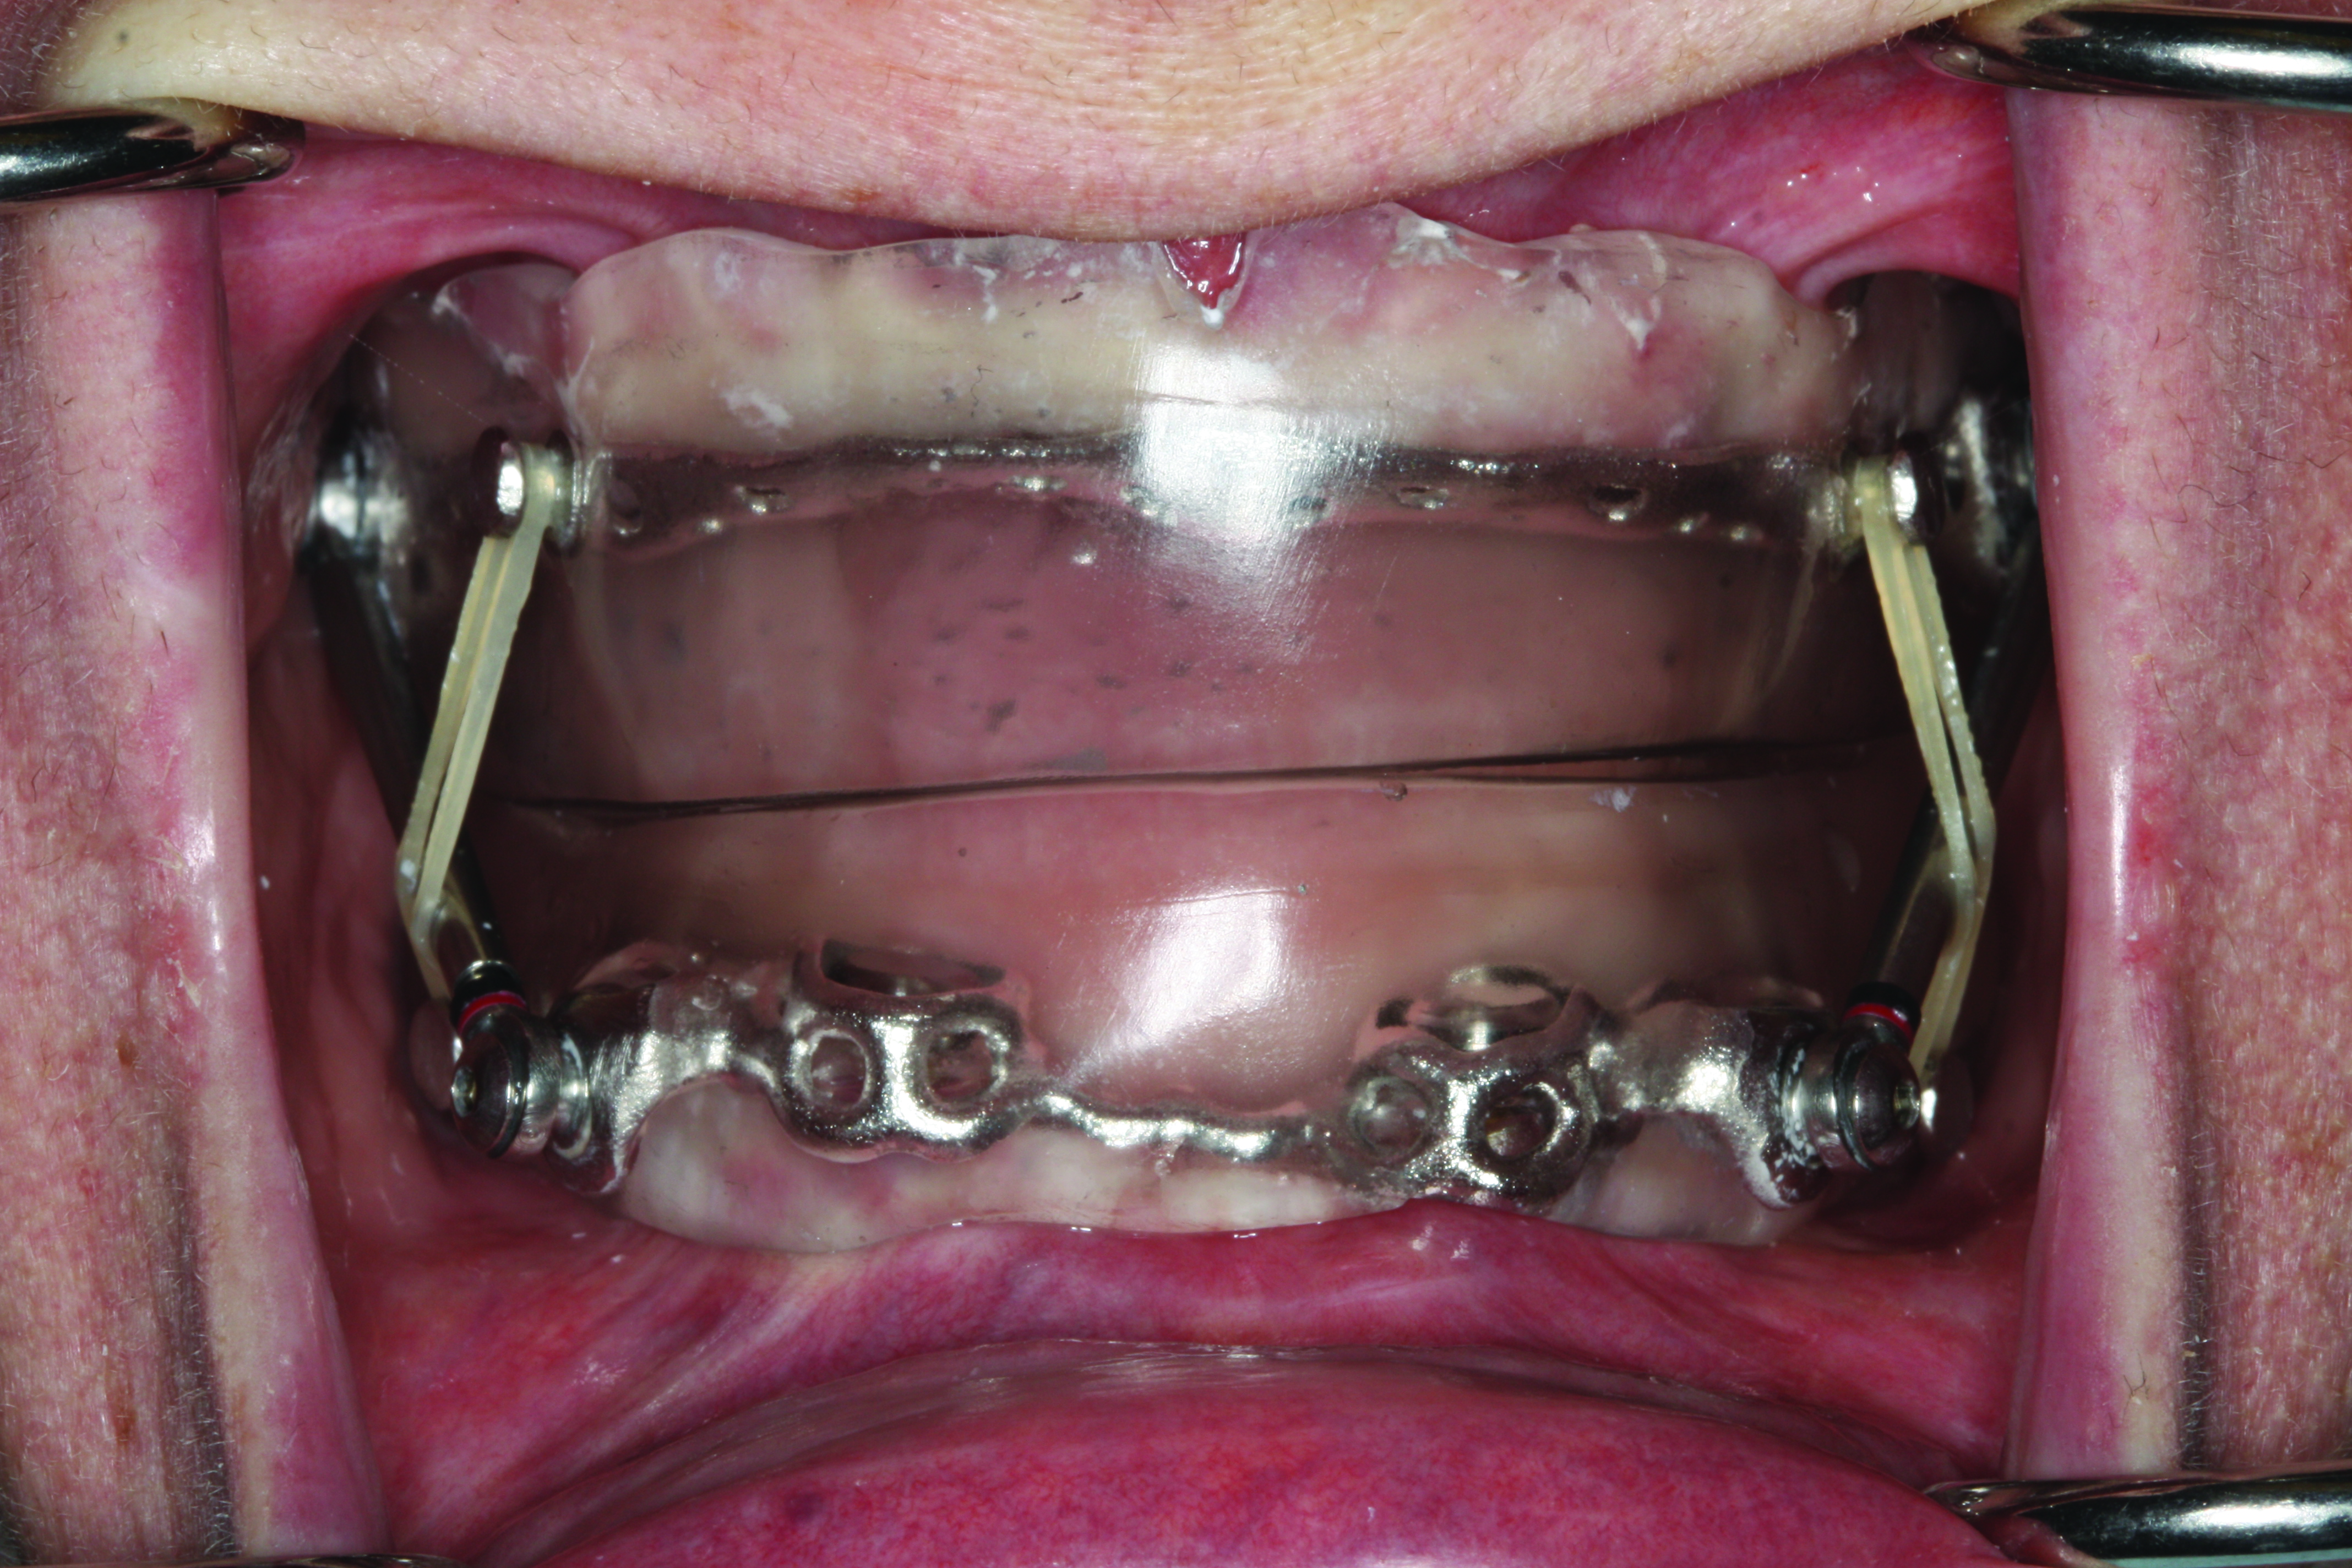

A patient’s candidacy for oral appliance therapy is determined based on careful evaluation of the dentition, periodontium, oral soft tissues, masticatory muscles, and TMJ. A sufficient number of teeth (ideally, eight in each arch) without decay or faulty restorations and of sufficient height to retain the oral appliance must be present, although mandibular advancement devices (MADs) can be supported by dental implants (Figure 1).1 Any active periodontal disease should be treated. The alveolar bone level should be adequate to withstand forces applied by the appliance. The presence of temporomandibular disorders per se is not a contraindication to oral appliance therapy. However, some patients will not be able to tolerate jaw advancement, while others may benefit from it.2 Based on the sleep study report and the orofacial examination, the dentist determines whether the patient is a good, guarded, or poor candidate for MAD therapy.

Fig 1. Edentulous patient treated with a MAD (SUAD Herbst appliance: http://www.strongdental.com/). The upper component is fit and contoured similar to the patient’s full upper denture. The lower component is retained by two dental implants with Locator® abutments (http://www.zestanchors.com/ ).

Fig 1. Edentulous patient treated with a MAD (SUAD Herbst appliance, strongdental.com). The upper component is fit and contoured similar to the patient’s full upper denture. The lower component is retained by two dental implants with Locator® abutments (zestdent.com).